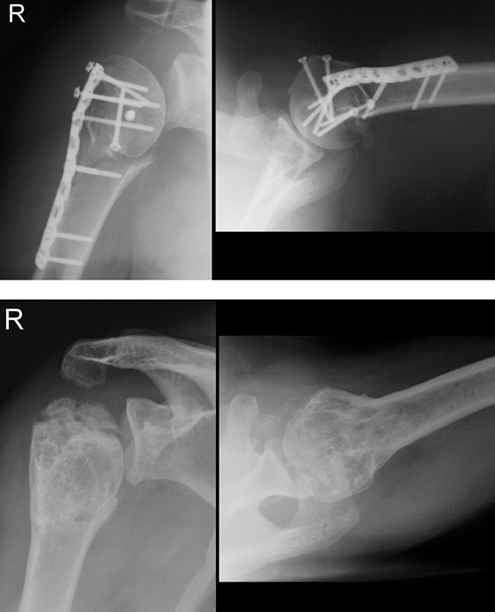

Re: Ищу Rg снимки пациентов с асептическим некрозом головки плеча после остеосинтеза пластинами с угловой стабильностью

Рис. 31-11. из Rockwood & Green "Fractures in adults" (2006).